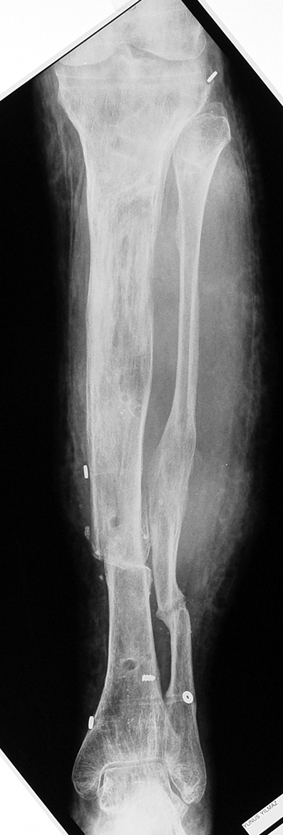

Appropriate radical debridement necessitates excision of all necrotic bone and soft tissues, and frequently causes instability at the involved extremity. The remaining bone and soft tissue defect has to be fixed and reconstructed. The distraction osteogenesis method of Ilizarov is used successfully for achievement of union, correction of the deformity, elimination of limb length inequality and reconstruction of segmental bone defects.

The duration of external fixation (external fixation index) depends on the amount of distraction required, and the extremity is prone to complications during this period. After the distraction phase is completed, the external fixator remains in place during the consolidation phase, which lasts twice as long as the distraction phase; but this period is hardly tolerated. If the external fixator is removed before sufficient consolidation is achieved, fractures, deformity and shortness will be the result. In our department, ‘lenghthening over nail’ method is used in order to decrease the external fixation index and increase patient comfort and activity level. In this method, the intramedullary nail is statically locked after the completion of the distraction phase, and external fixator is removed. The extremity is stabilized by the intramedullary nail during consolidation phase. In this way, complications due to long external fixation index or early removal of the external fixator are avoided.